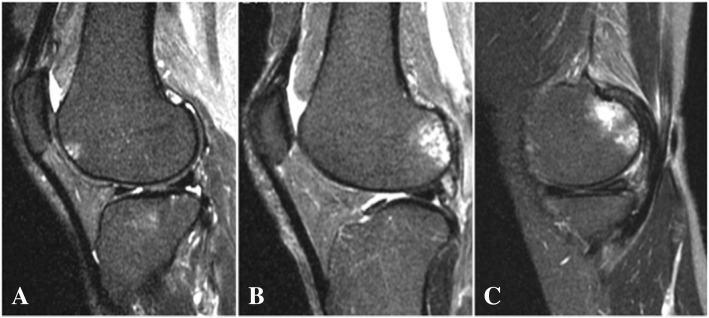

All participants underwent MRI of the right knee using a rapid extremity coil and mobile magnetic resonance unit (1.5 T; ECHELON RX, Hitachi, Tokyo, Japan) within 1 week after other examinations. The participants were positioned supine with their knees in full extension. Sequences included sagittal and coronal T2-weighted fat saturation fast spin echo (repetition time 5000 ms; echo time 80 ms; field of view 16 cm; 288 × 288 matrix; slice thickness of 3 mm with a between-slices gap of 1.0 mm). BMLs were defined as the area of an irregular hyperintense signal in the subchondral bone. The area was measured semi-quantitatively using the Whole-Organ MRI Scoring (WORMS) method [28] in 15 subregions. Specifically, the medial and lateral compartments of the tibia and femur were divided into 3 subregions (anterior, central, and posterior), and the tibia had 1 additional subregion, representing the area beneath the tibial spine. The patella was divided into medial and lateral subregions (Fig. 1). BMLs were each scored as integers from 0 to 3, where 0 = normal; 1 = mild, < 25% of the region; 2 = moderate, 25–50% of the region; and 3 = severe, > 50% of the region (Fig. 2). The total BML score, which reflected severity, was calculated as the sum of the 15 subregional scores. BML was considered present if the total BML score was greater than zero. Two independent observers (DC and ES) scored MR images in a blinded fashion with no access to the participants’ clinical information. The inter-rater reliability, expressed as interclass correlation coefficients [ICC] (2.1) of scoring BML on 100 randomly selected MR images, was 0.873 (95% confidence interval [CI] 0.815–0.914, p < 0.001).

Fig. 2.

Evaluation of bone marrow lesions (BMLs). BMLs were measured using the coronal and sagittal T2-weighted images and marked by the increased signal intensity area in the subchondral bone. BMLs were graded according to the percentage of the area according to the Whole-Organ MRI Scoring method. a Grade 1 BML in the anterior lateral femur. b Grade 2 BML in the posterior lateral femur. c Grade 3 BML in the posterior medial femur